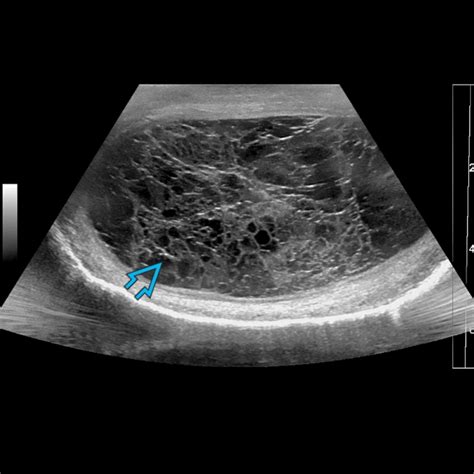

So, you’ve recognized some concerning symptoms, and now you’re wondering, “What’s next?” It’s time to talk about diagnosis and treatment for orchitis and epididymitis . The most important step, guys, is to seek medical help immediately if you suspect you have either of these conditions. Don’t delay! A healthcare provider will start by taking a detailed medical history and performing a physical examination. They’ll check for swelling, tenderness, and redness in the testicles and scrotum. They might also check for any signs of infection elsewhere, like in the urethra or prostate. To confirm the diagnosis and identify the specific cause, several tests might be ordered. A urinalysis can detect signs of infection in your urine. A urine culture can identify the specific bacteria causing the infection. If an STI is suspected, a swab from the urethra or a urine sample can be tested for chlamydia and gonorrhea. In some cases, a doctor might order an ultrasound of the scrotum. This imaging test uses sound waves to create detailed pictures of the testicles and surrounding structures. It’s particularly useful for ruling out other serious conditions like testicular torsion and can help visualize the inflammation in the testicle or epididymis. Once the diagnosis is confirmed, treatment for orchitis and epididymitis typically focuses on eliminating the underlying infection and managing the symptoms. If a bacterial infection is identified, antibiotics are the cornerstone of treatment. The type of antibiotic prescribed will depend on the specific bacteria identified and whether it’s an STI-related infection or one stemming from the urinary tract. It’s absolutely critical to finish the entire course of antibiotics, even if you start feeling better, to ensure the infection is fully eradicated. For viral infections like mumps orchitis, antibiotics won’t help, and treatment is usually supportive, focusing on rest and pain relief. Pain and inflammation are managed with over-the-counter or prescription pain relievers like ibuprofen or naproxen. Applying a cold compress to the scrotum can also help reduce swelling and discomfort. Resting, elevating the scrotum with a supportive bandage (like an athletic supporter), and avoiding sexual activity during treatment are also important recommendations. In more severe cases, such as if an abscess (a collection of pus) forms, hospitalization and drainage might be necessary. So, understanding the meaning of orchitis and epididymitis goes hand-in-hand with knowing that prompt diagnosis and appropriate treatment are essential for a full recovery and to prevent long-term complications. Don’t hesitate to reach out to your doctor – they’ve got your back!